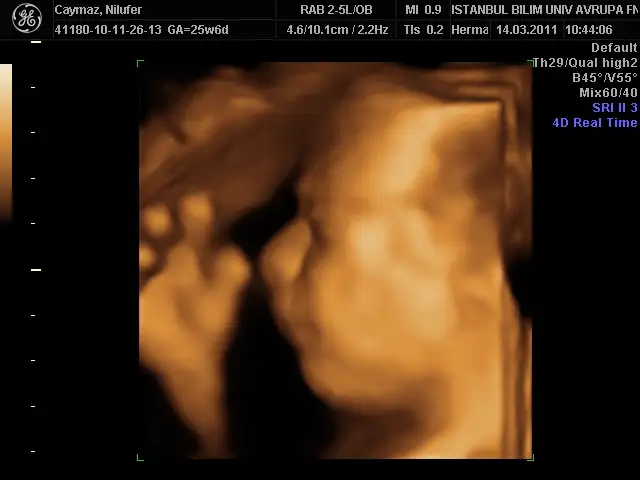

benimki 35 cm 1056 gr olmuş annesinin gülü dr önce rahmi çok ince budu 2,7 mm sonra sıkıştık tuvalalete öyle baktı çok şükür bir problem yokmuş bu sefer yüzünü bizden gizlemedi oğluşumm bence bana benziyor babasını kıl ediyorum bana benziyor diye kız olsa anlarım bana benzesin triplerini de diyor bu erkek banabenzicek diyo bi kıskanıyor bi kıskanıyor çok hoşuma gidiyorr

alın sıze teyzelerı suratsız oglum:))

yelkovan resimler super seninkisi pek dertli gorunuyor iceride bir buyuk devirmis gibi))) masallahhhhhhhhh